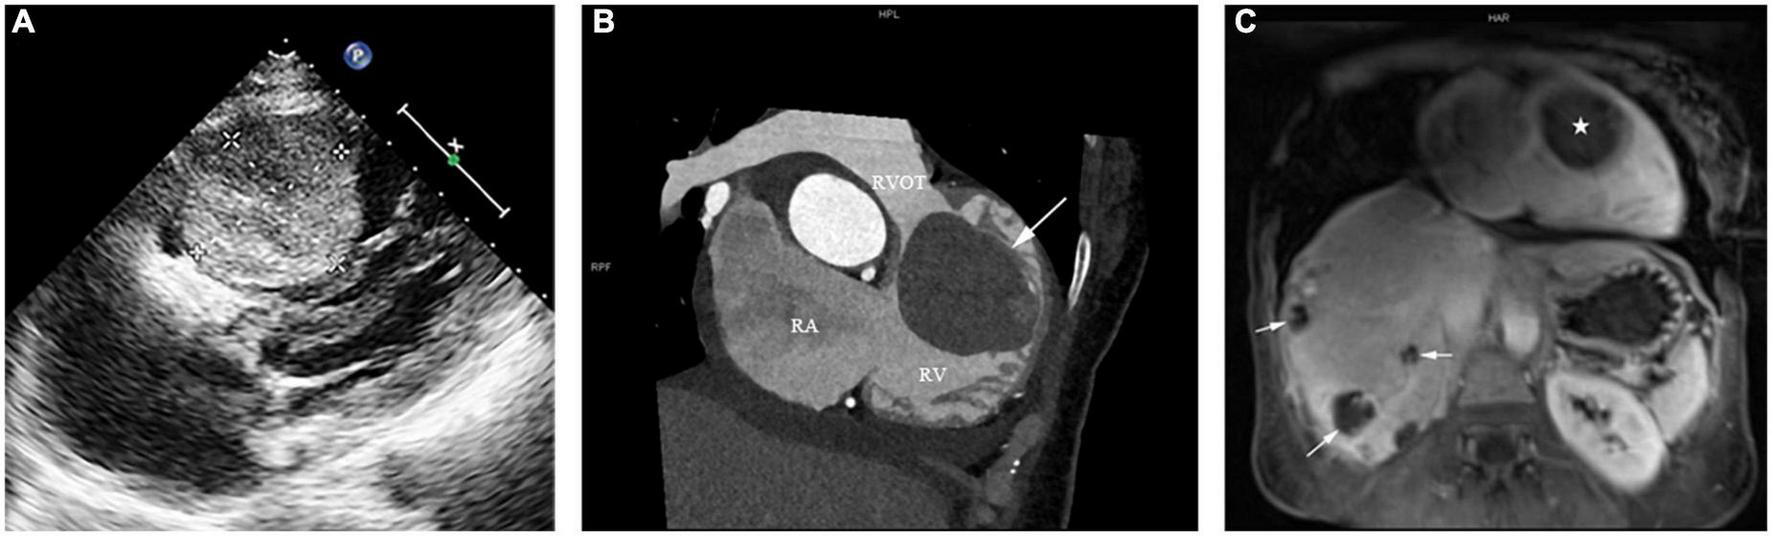

Echocardiography revealed a large solid mass (4.82 cm × 4.48 cm × 6.42 cm) (Figure 1A), with right ventricular outflow tract obstruction and secondary severe tricuspid regurgitation (Video 1). No abnormal echoes were detected in the pericardium or pericardial cavity. Computed tomography (CT) scan revealed right ventricular mass (Figure 1B), along with multiple occupancies in the liver. A diagnosis of breast cancer metastasis was suspected at first. Magnetic resonance imaging (MRI) was performed to further define the mass of these two organs. The cardiac mass (Figure 1C) showed iso-intensity on T1-weighted images and hyper-intensity on T2-weighted images compared with the normal myocardium of the right ventricle. The mass showed diffuse contrast uptake with gadolinium enhancement. Further, evaluation of the liver revealed multiple mass lesions with varied sizes showing progressive enhancement, indicating a typical VM (Figure 1C). Notably, the lesions of two organs were not detected in previous assessments of breast cancer.

(A) Preoperative transthoracic echocardiography showing a large mass measuring 4.82 cm × 4.48 cm × 6.42 cm attached to the anterior wall of the right ventricle, with a moderate to strong and relatively homogeneous echo. (B) The computed tomography scan of the patient’s chest showing a right ventricular mass (arrow) in the right ventricular outflow tract (RVOT). RA: right atrium; RV: right ventricle. (C) Reconstructed magnetic resonance imaging of the patient’s chest and abdomen showed a cardiac mass concurrent with multiple hepatic lesions. The right ventricular mass and the multiple liver lesions are indicated by a star and three arrows, respectively.